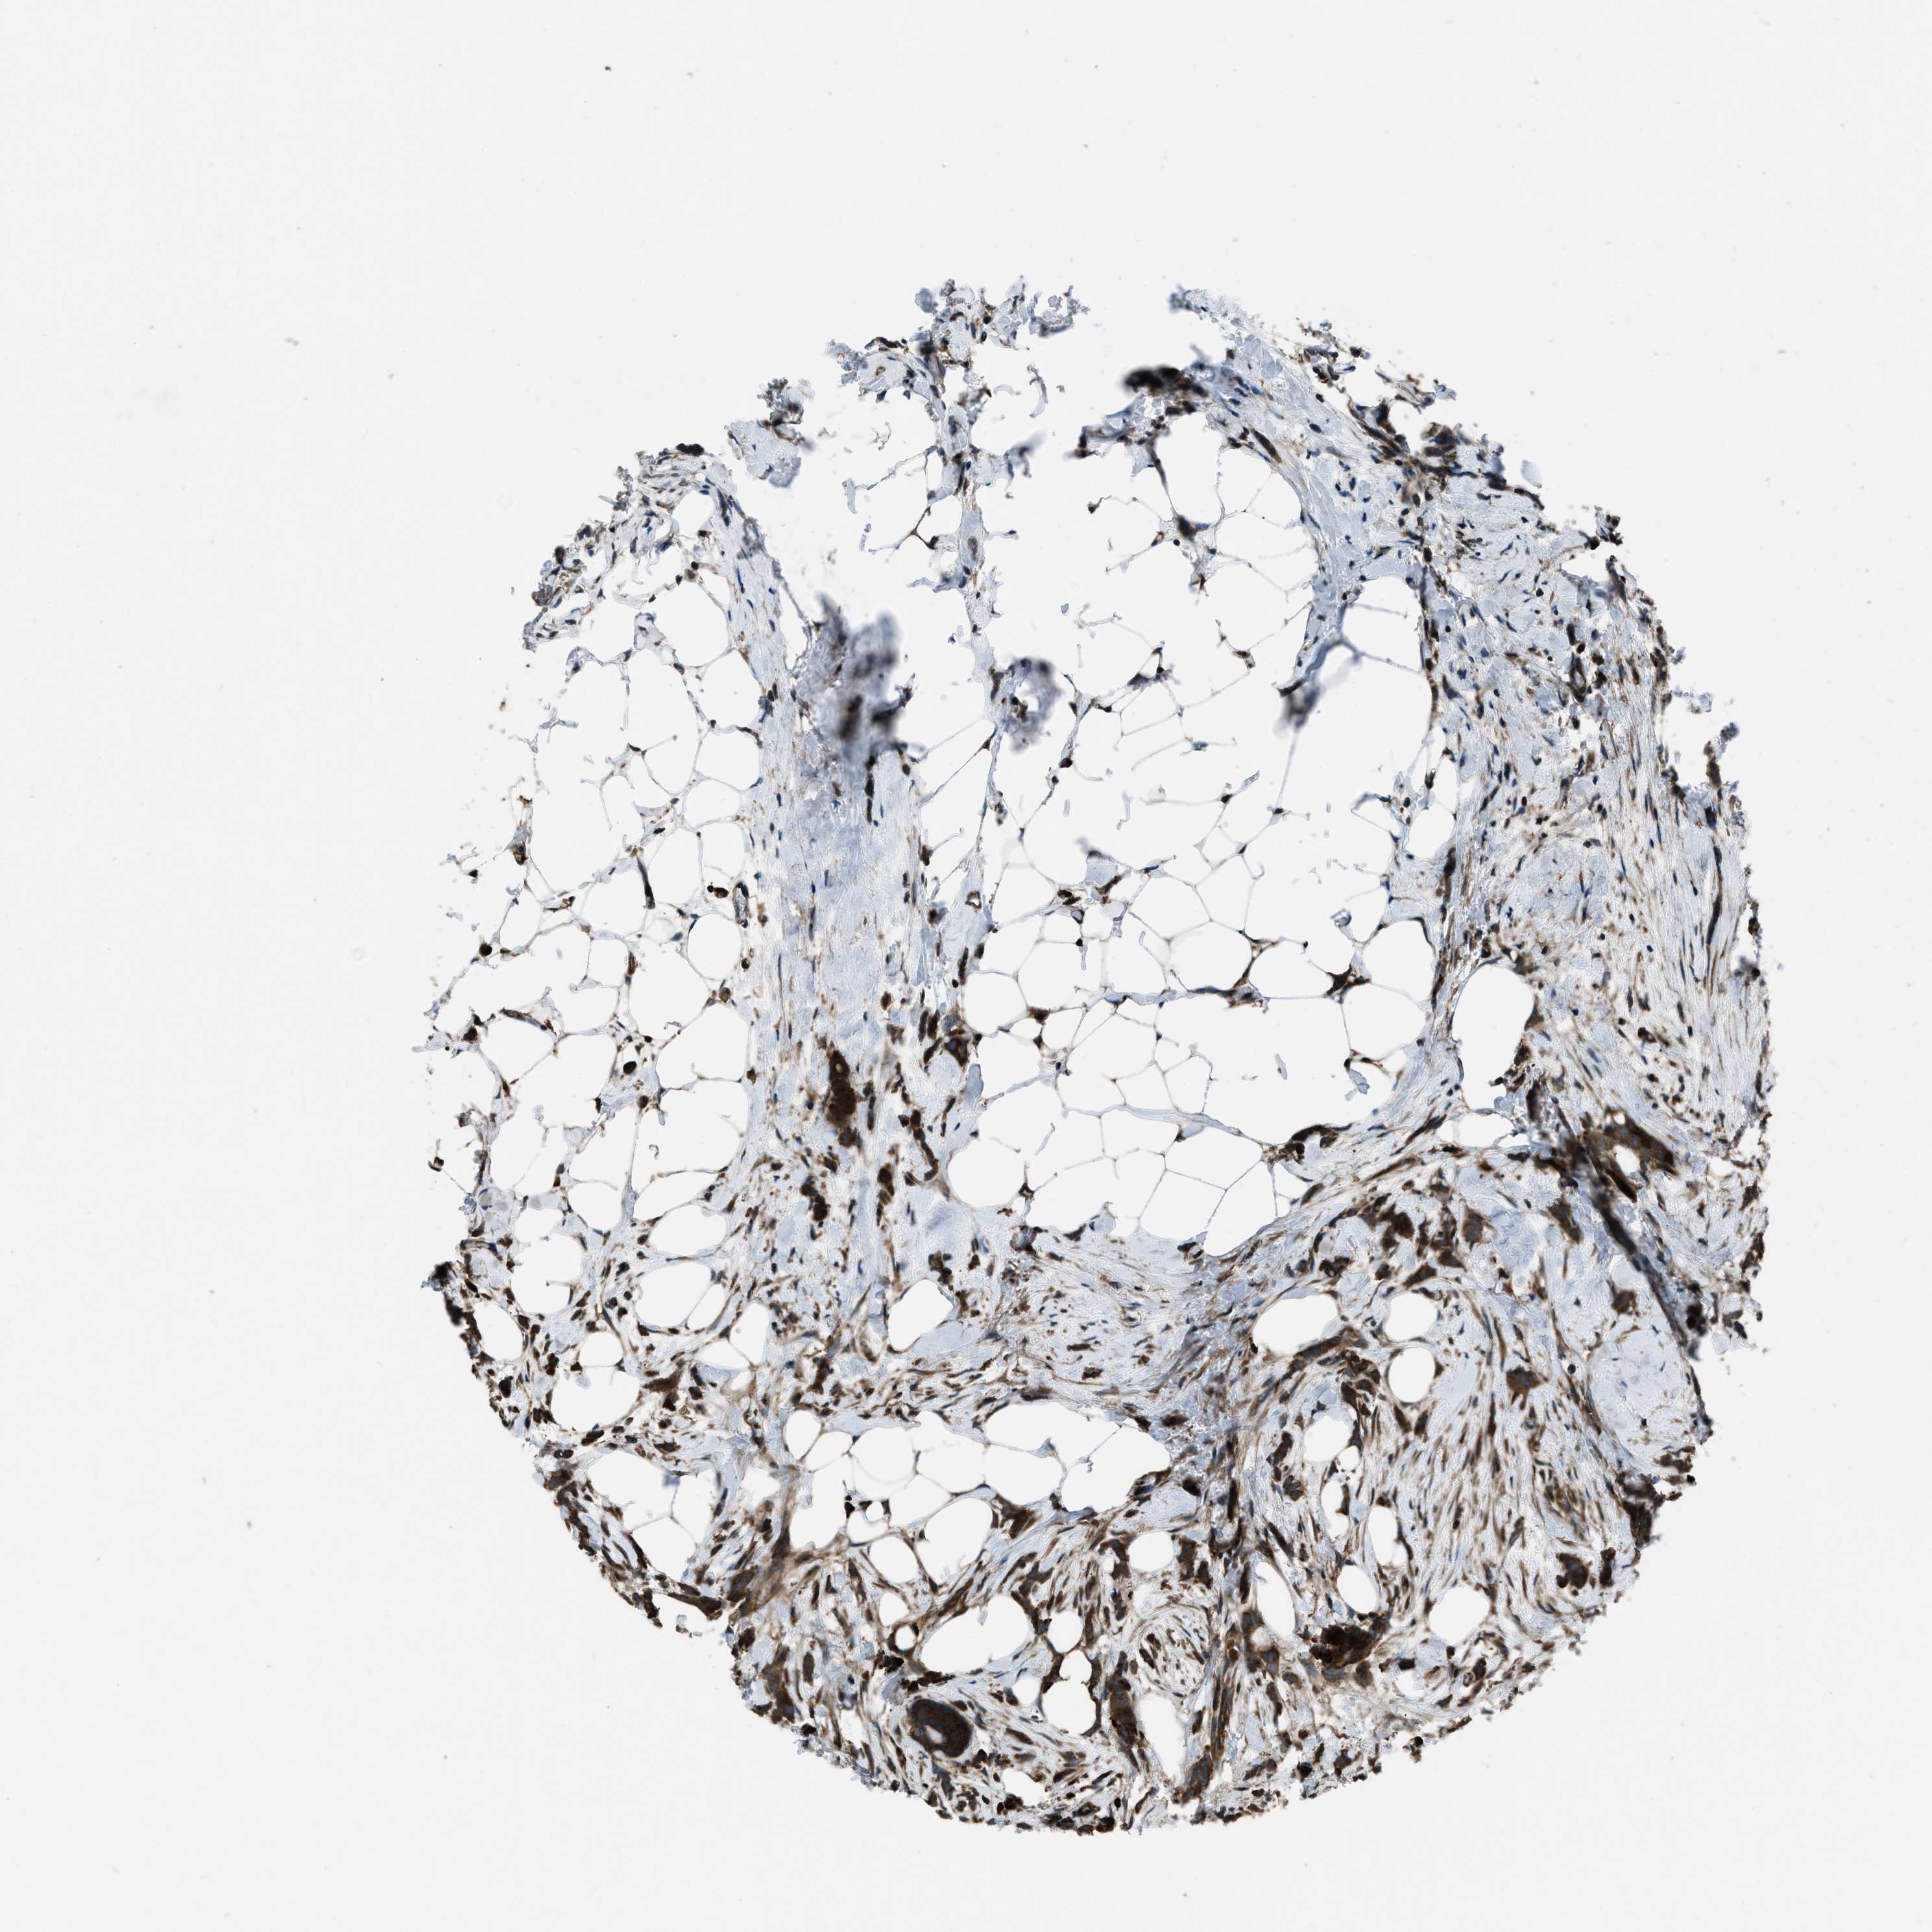

CANCER BREAST CANCER Show tissue menu

BRCA TCGA BRCA VALIDATION PROTEIN EXPRESSION